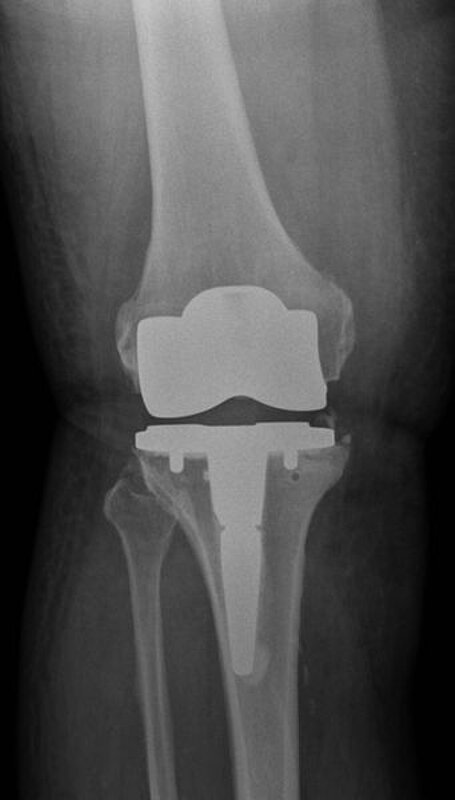

Kurze Vorgeschichte: Herr S, ein 67-jähriger Patient, erhielt 2011 (Abbildung 1) bei ausgeprägter Gonarthrose eine primäre KTEP rechtsseitig. Im weiteren Verlauf zog er sich 2017 eine periprothetische Tibiafraktur zu, die mit einem Knieendoprothesenwechsel auf ein achsgeführtes Implantat (Abbildung 2) und Schaftverlängerung der Tibia im September 2017 ex domo therapiert wurde. Im Verlauf zeigten sich eine anhaltende Sekretion und eine partielle Nekrose am unteren Wundpol.

Eine Röntgendiagnostik des rechten Kniegelenkes in 2 Ebenen wurde eingeleitet. Hierbei zeigte sich eine stabil einsitzende Revisionsprothese ohne aktuelle Lockerungszeichen.

Im weiteren Verlauf zeigten sich die Weichteile des rechten Unterschenkels zunehmend mazeriert und belegt. Zudem sei der Patient erneut gestürzt. Eine erneut durchgeführte Röntgendiagnostik zeigte erneut eine periprothetische Tibiafraktur (Abbildung 3) bei einliegender achsgeführter KTP mit langem tibialem Stem und bekanntem periprothetischem Infekt mit Candida parapsilosis. Wir haben die Befunde ausführlich mit dem Patienten besprochen und in Zusammenschau der Befunde schließlich die Indikation zur Oberschenkelamputation gestellt.